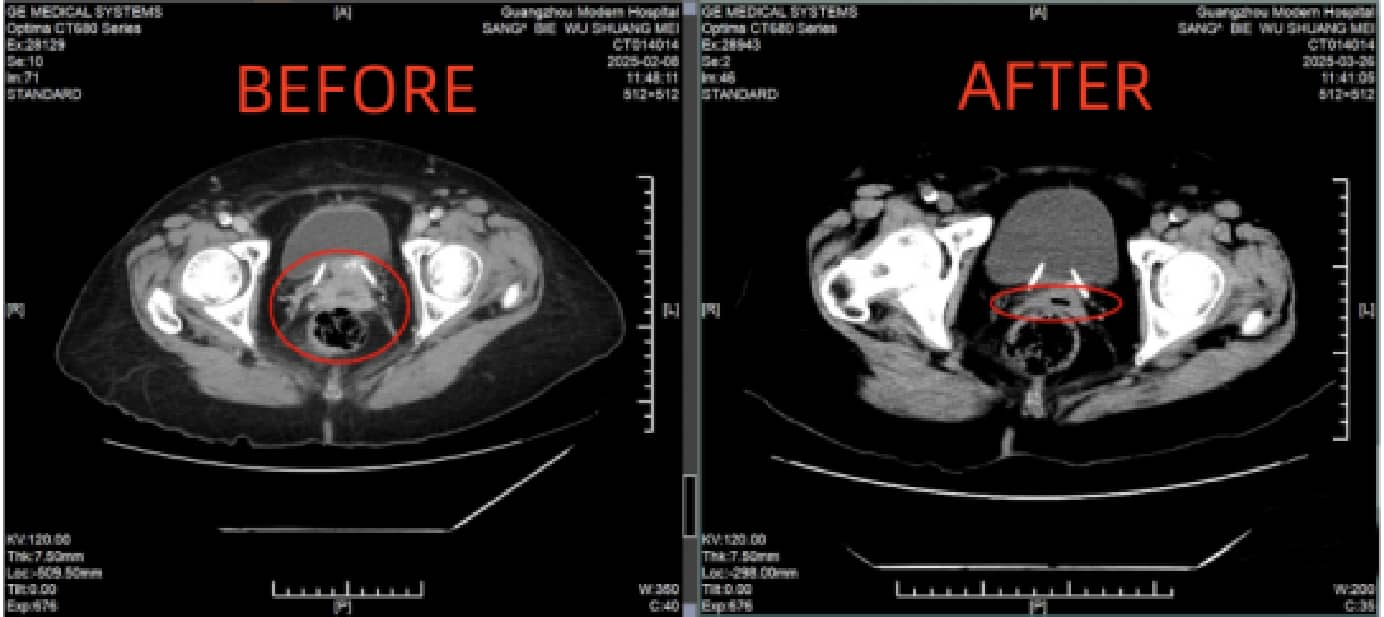

Diana Kartika Arma,

Diana Kartika Arma, kanker serviks stadium IB2B - telah bertahan 3 tahun.

Diana, seorang wanita Muslim yang berusia 57 tahun dari Jakarta, Indonesia, adalah sosok yang kuat dan tidak mudah menyerah. November 2021, ia mengalami perdarahan vagina yang tidak normal, setelah menjalani pemeriksaan, ia didiagnosis menderita kanker serviks stadium IB2, dan berat badannya turun hingga 8 kg.

Sebelum pengobatan VS setelah pengobatan

Oktober 2024, Diana datang ke Modern Cancer Hospital Guangzhou untuk mendapatkan pengobatan. Setelah menjalani rangkaian pengobatan yang disesuaikan dengan kondisinya, tumor berukuran 1.5 × 1.2 × 2.9 cm serta gejala perdarahan dinyatakan “hilang sepenuhnya”. Saat ini, kualitas hidupnya meningkat signifikan : tidur lebih nyenyak, nafsu makan membaik, dan berat badan naik kembali. Ia kini dapat menjalani hidup dengan kondisi yang jauh lebih baik.